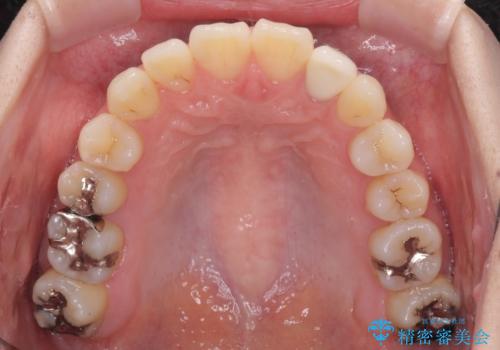

抜歯矯正は2年から2年半程度の治療期間を要することが一般的ですが、僅か1年1ヶ月で終了しました。

あっという間に気になっていた歯並びが改善し、患者様には大変満足していただきました。